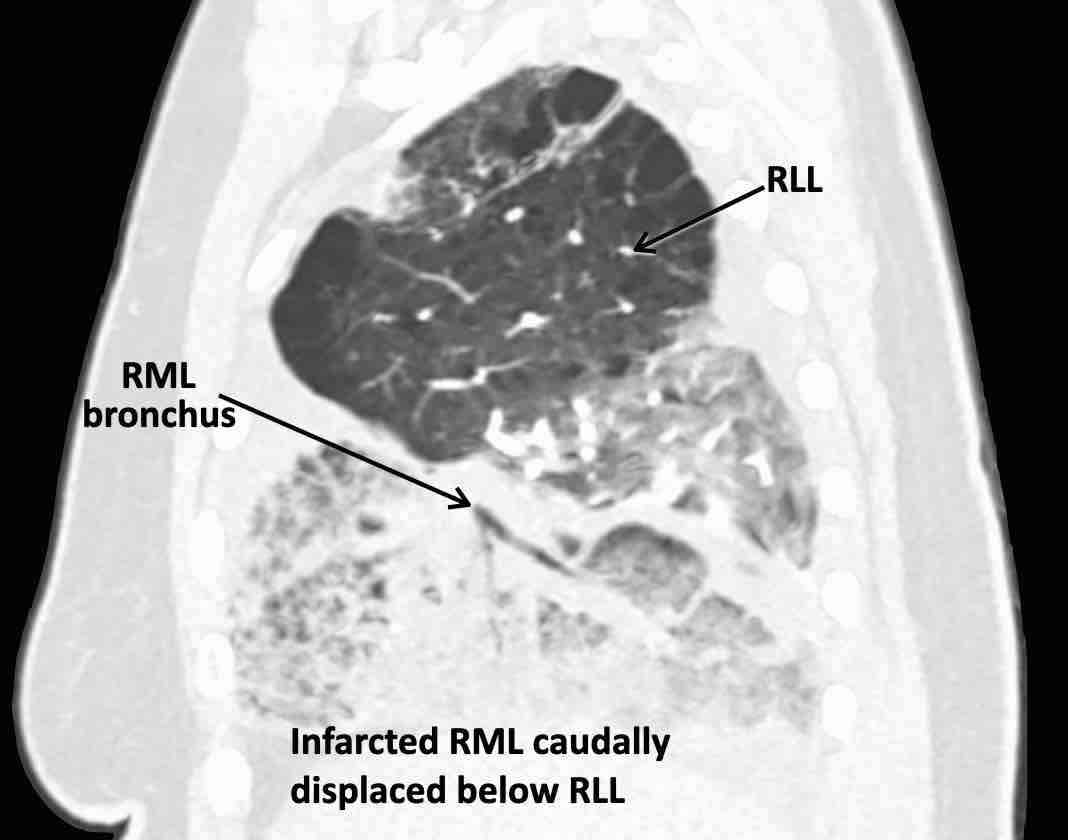

Các hình ảnh này của một bệnh nhân nữ 65 tuổi sau khi đã cắt thùy trên phổi phải trước đó.

Theo dõi lần lượt các phế quản giúp xác định mỏm cắt thùy trên phổi phải (RUL), phế quản thùy giữa bị tắc nghẽn và các phế quản thùy dưới còn thông.

Điều này xác định mô phổi bị di lệch xuống dưới chính là thùy giữa phổi phải (RML), thấy rõ nhất trên mặt phẳng đứng dọc.

Thùy giữa phổi phải bị phù nề và không còn được tưới máu.

Ngoài ra còn thấy hình ảnh ứ máu và xẹp phổi ở các phân thùy đáy của thùy dưới phổi phải (RLL), hiện nằm phía trên thùy giữa phổi phải đã bị nhồi máu.